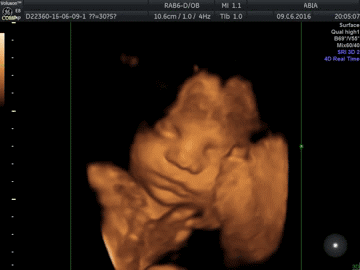

Во втором триместре беременности у ребенка активно развивается мимика — именно сейчас вы сможете увидеть его первую улыбку! Малыш сосет пальчик и хмурится, Вы уже можете распознать его ушки, глазки и носик... на небольшом сроке беременности на УЗИ можно увидеть ребенка во весь рост.

В 30-35 недель беременности малыш уже похож на новорожденного ребенка, у него даже есть ресницы, ногти, а иногда и волосы на голове! Увидеть своего кроху в это время – наивысшее счастье для каждой мамы!